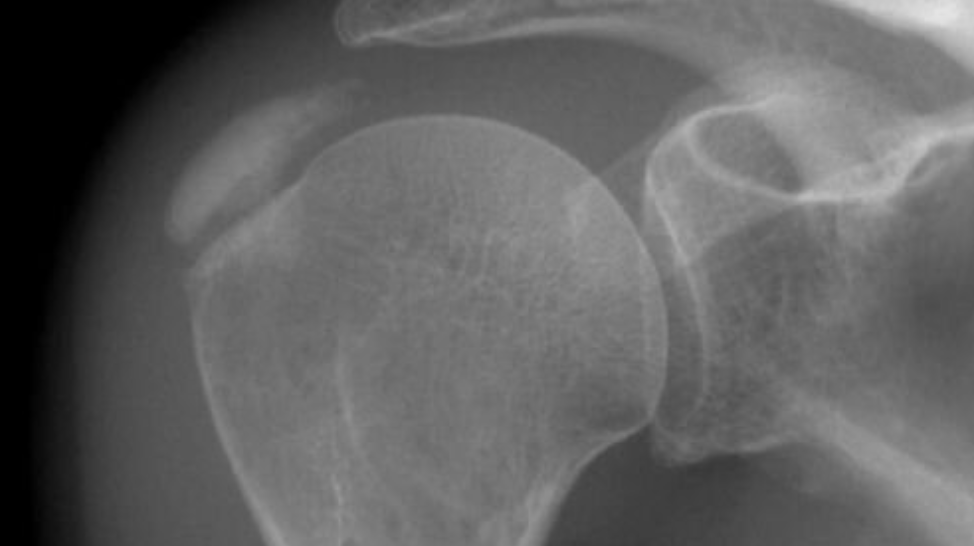

Mr Moverley may request a repeat x-ray on the morning of surgery to make sure the calcium deposit is still present.

Calcific Tendonitis